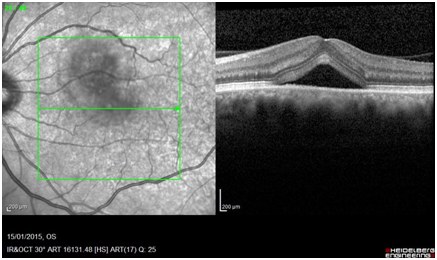

Figure 2E & 2F, OCTs showing macular detachment in both eyes. Notice that in the right eye the detachment is severely tabicated.

Biochemistry, microbiology and autoimmunity parameters were normal. HLA-DR4 was positive. The patient was treated with oral steroids prednisone 60 mg every 24 hours and omeprazole, 20 mg c/24h. A week later, the VA's OI has improved to 20/30 and the exploration of the fundus and the OCT showed a decrease macular neurosensory detachment striking her left eye. After a month of treatment, VA was 1 in both eyes and the fundus and OCT scan were normal (Figure 2G&2H).

Figure 2G & 2H, OCTs revealing serous macular detachment resolution in both eyes. Retinographies show restauration of fundus images in both eyes.

Caucasian woman aged 22 who attends derived from another center with a diagnosis of unilateral CRCS after abruptly presented severe decrease in visual acuity (VA) in her left eye.Do not have a personal or family history of interest. The picture is not accompanied by systemic signs or symptoms. On examination, VA is 20/20 in her right eye and counting fingers in her left. The IOP is normal in both eyes. The anterior segment examination shows no signs of inflammation. The fundus examination shows a brightening of the internal limiting membrane in the posterior pole of both eyes and a macular neurosensory detachment with a brownish hue in the left eye (Figure 2A&2B). The FA shows hyper fluorescent macular lesion in the right eye with multiple hyper fluorescent spots inside, taking a look of “starry night”, and hyper fluorescence of the optic disc in both eyes (Figure 2C&2D). The OCT of the right eye shows large loculated neurosensory detachment in the macular area. The OCT of the left eye shows neurosensory detachment (Figure 2E& 2F).